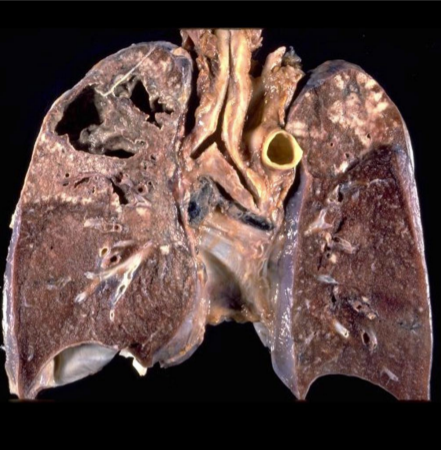

What is this?

Cavitating TB